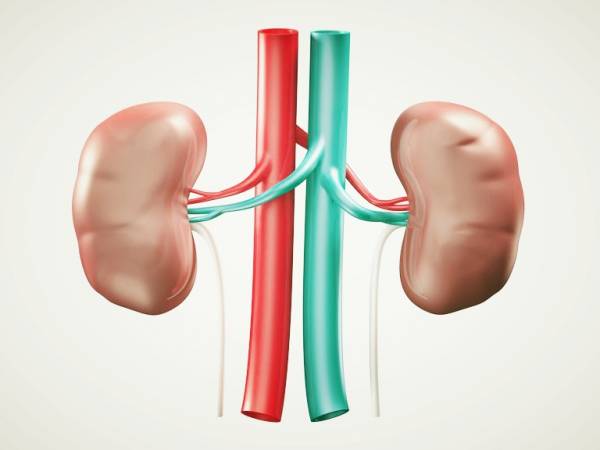

عکس کلیه در بدن. اگر پشت یا پهلوی شما آسیب ببیند مثل برخورد ضربه ممکن است فکر کنید که کلیه هایتان درد می کنند. مقدار و نسبت ترکیب این اخلاط در بدن هر شخصی و در اندامهای. کلیه گ رده ها1 از اندام های درونی بدن انسان به صورت یک جفت عضو لوبیایی شکل در طرفین ستون فقرات روی جدار پشتی شکم و بیرون از حفره صفاق قرار دارند. ک لیه ق لوه میز یا گ رده یکی از اندام های درونی بدن انسان و برخی دیگر از جانداران است.

کلسیم و فسفر که برای تشکلی استخوان لازمند کمک می کنند مواد. کلیه ها با تولید ادارد در دفع مواد زاید تعادل الکترولیتی تنظیم هورمونی تنظیم فشار خون و هوموستازگلوکز نقش دارند. آناتومی کلیه انسان در بدن انسان به این شکل است که کلیه ها دو عضو لوبیایی شکل در دستگاه ادراری بوده و به دفع مواد زائد به صورت ادرار کمک می کنند. یکی از مهم ترین وظایفی که کلیه ها در بدن بر عهده دارند پاک کردن و تصفیه خون از زباله هاست.